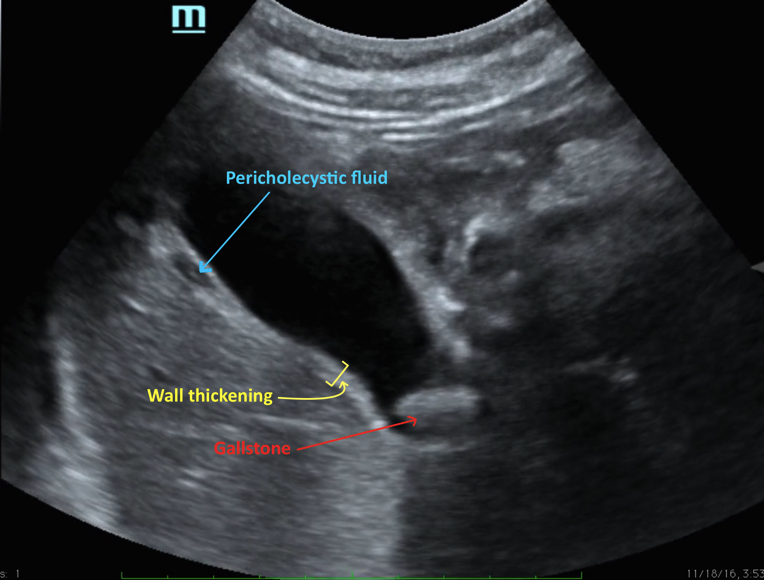

Back to the case: you are able to get a rapid abdominal ultrasound, which reveals the following:

Gallbladder wall thickening

Stones present in the gallbladder

Pericholecystic fluid

Sonographic Murphy’s sign

This is a slam dunk case of acute cholecystitis, and a referral to general surgery for management is warranted.